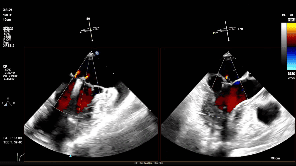

随后将可操控导引导管(SGC)及二尖瓣夹输送系统(CDS)送入左心房。仔细调整XTW二尖瓣夹的轨迹和方向后,进行首次夹合,超声提示仍存在少量二尖瓣反流,考虑为后侧瓣叶捕获不足所致,且侧边瓣叶仍存在明显脱垂。遂打开夹臂,在左心房内调整夹子位置,向后侧、外侧移动,以捕获更多后侧瓣叶,再次夹合,成功解决反流与脱垂问题,测得术后平均压差为4mmHg,手术圆满成功。

超声提示仍存在少量反流

第一次夹合后3D

第一次夹合后3D彩

调整瓣膜夹位置

再次捕获瓣叶

第二次关闭瓣膜夹

测量前后瓣距离

释放夹子

夹子释放后反流降至轻度

3D下组织桥稳定

3D下上彩

术后平均压差为4mmHg